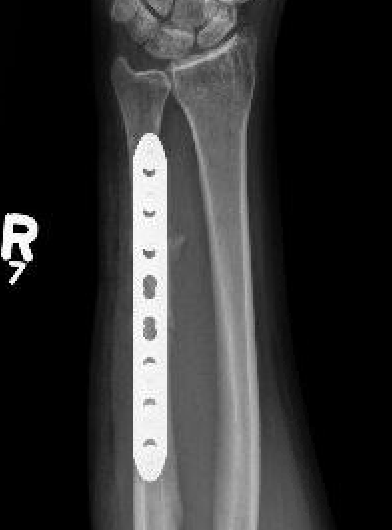

Operative management

Indications

Acute fractures

- > 50% displacement

- > 10 degrees angulation

Options

Compression plating